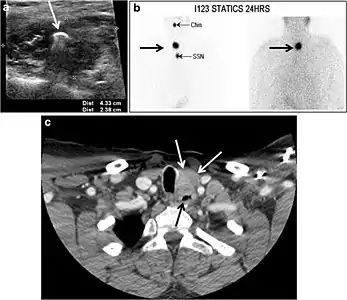

Ectopic thyroid tissue may be detected in the tongue near the foramen cecum (90%) and along the midline between the thyroid isthmus and posterior tongue, lateral neck, mediastinum, and oral cavity. The most frequent location is the base of the tongue (Figs. 16, 1717 and and18).18). In 70% of cases, the ectopic thyroid is the only functional thyroid tissue present in the body (Fig. 18).[1]

Fig. 18. Lingular thyroid in a 33-year-old male who presented with oropharyngeal bleeding. an Axial enhanced neck CT scan at the level of mandible demonstrates a 3 × 3 × 3.4 cm round, partly well-delineated, heterogeneously enhancing lesion (white arrow). It is predominantly on the left side of the oropharynx and to some extent at the mid part of the base of the tongue. Thyroid gland was normal (not shown). b Image of the anterior face and neck taken 20 minutes after Tc99m-Pertechnetate injection shows absent thyroid radiotracer uptake in normal thyroid anatomical location (black short arrows). There is an area of increased uptake (long black arrows) corresponding to posterior tongue mass identified on CT scan.[1]

Ectopic thyroid tissue lateral to the orthotopic midline location is rare. The exact anatomical definition of this rare entity is debated in the literature. To avoid confusion, some authors define a lateral neck ectopic thyroid as any thyroid tissue superficial to the strap muscles with no midline continuity. The majority of lateral thyroid ectopia cases have been reported as lesions closely related to the strap muscles. There are few reported cases of ectopic lateral thyroid tissue in the submandibular region, jugulodigastric region, or within the parotid gland substance (Fig. 17).[1]